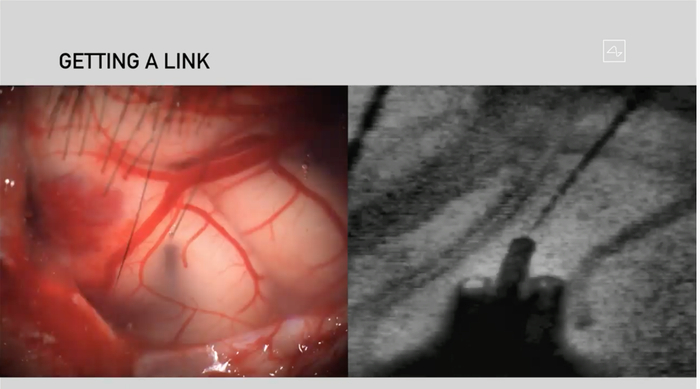

直播现场展示了猪脑活动的实时无线传输。当猪的鼻子触碰到物体时,图像上出现噪音。

读取大脑活动